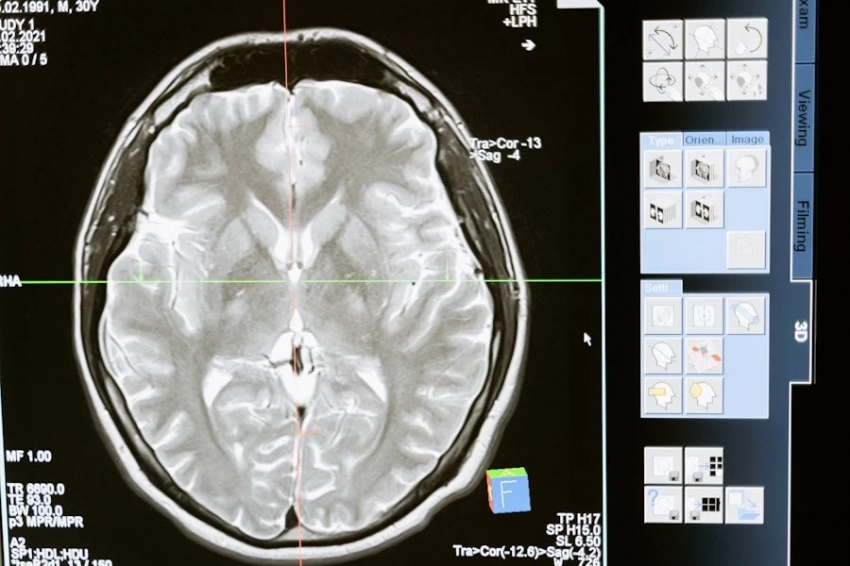

Naegleria fowleri прозвали «амебой, поедающая мозг», поскольку она инфицирует головной мозг. Ученые отмечают, что амеба попадает в организм с зараженной водой через нос, распространяется по нервам и попадает в мозг. Там она начинает размножаться и параллельно разрушать ткани этого органа.